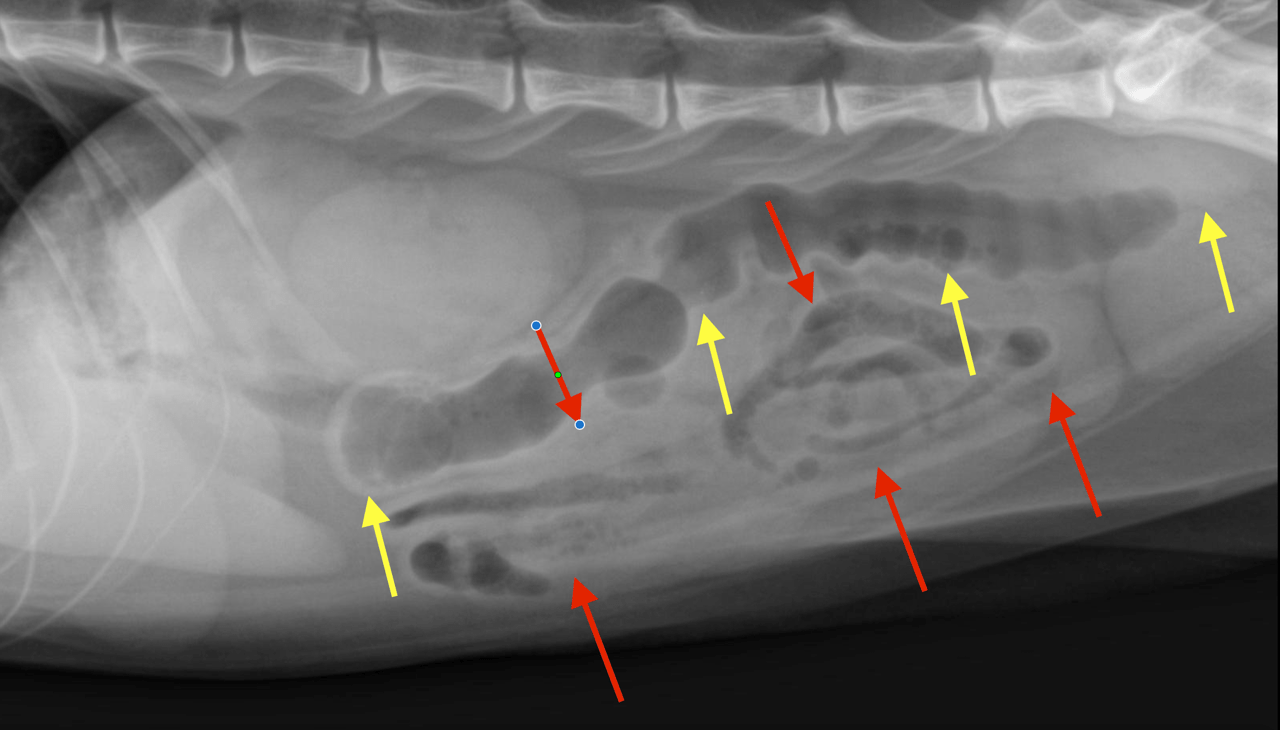

Physical Exam: EENT – squinting, yellowish nasal discharge; saline in nose does not make him sneeze PLN – normal HL – clear – Abdomen – fluid, diarrhea greenish mucoid despite all meds (metronidazole, propectalin); possible long item in bowel palpated dorsally. URTI, Diarrhea, Anemia, Weight loss, Anorexia